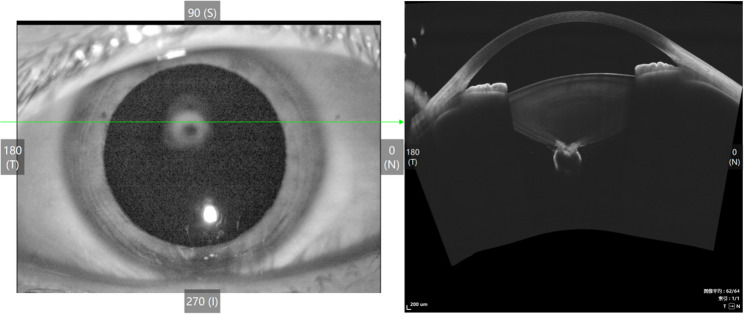

后极性白内障合并玻璃体囊肿。

Posterior polar cataract combined with vitreous cysts.